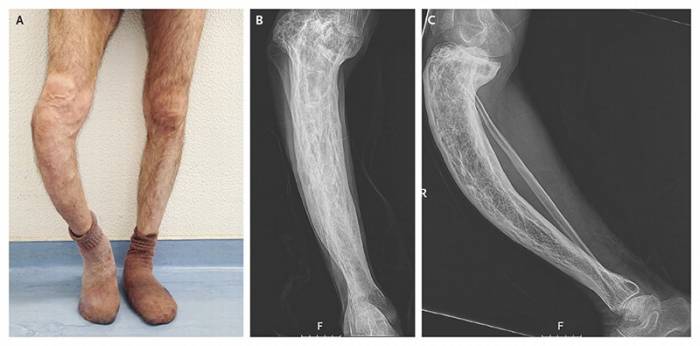

Патология поражает кости, меняется рециркуляция веществ, старая костная ткань постепенно замещается новой. Патологические изменения приводят к серьезным нарушениям: деформации и хрупкости костей. Болезнь чаще поражает таз, позвоночник и нижние конечности (фото).

- Поражение ног вызывает слабость в теле, деформацию костей. Усиливается нагрузка на рядом расположенные суставы, что приводит к развитию остеоартрита. Чаще патологические процессы затрагивают бедра и колени.

Определить болезнь Педжета помогает рентген костей. Некоторым пациентам врачи дополнительно назначают биопсию. Тепловизионная процедура позволяет определить участки мягких тканей с высокой температурой над пораженными костями.